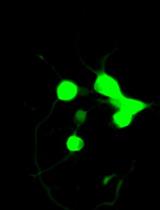

2. Observe the fluorescent properties of the prepared emulsion samples using a Leica TCS SP8 X inverted confocal microscope equipped with diode-pumped solid-state lasers (561 nm and 671 nm) focused through a 20×/0.70 N.A. objective (Figure 2B).

3. The Cy7 fluorescence is stimulated by a laser with a wavelength of 671 nm, and the resulting emission is measured in the range of 730–795 nm (green channel, Figure 2B).

4. The Nile Red fluorescence is activated by a laser with a wavelength of 561 nm, and the resulting emission is measured in the range of 580–650 nm (red channel, Figure 2B).